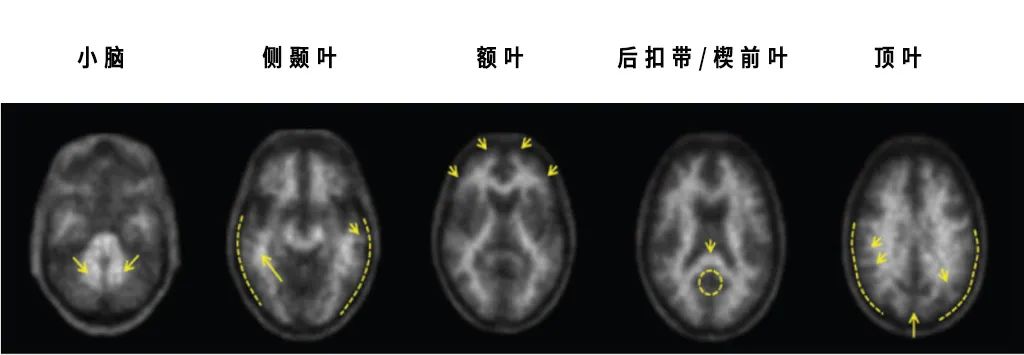

Neuraceq ®扫描图像显示阴性。灰质的显像剂摄取量低于白质,由AD导致认知能力下降的可能性降低

Neuraceq® 扫描图像显示阳性,灰质的显像剂摄取与白质相同或更高,β-淀粉样神经性斑块中度至频繁

▲(通过大脑不同区域对Neuraceq® 的摄取程度来估计β-淀粉样神经性斑块密度,图源:LMI官网)